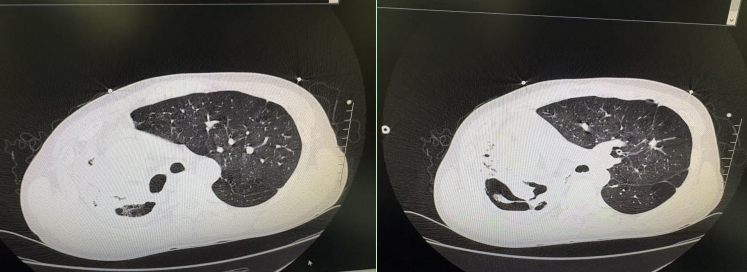

此时患者仍间断咯血,总量已达500毫升以上,生命体征持续恶化:心率升至 170 次 / 分,血氧饱和度降至 88%,呼吸次数达 35 次 / 分,左肺可闻及满布湿性啰音,大气道堵塞风险急剧升高。呼吸医学中心、麻醉科、手术室、影像中心团队同步响应,准备实施急诊镇静镇痛下大孔径支气管镜清除血栓+局部灌注止血药物止血手术,迅速开放气道,防止窒息进一步加重。最后,在卢晔教授的带领下,呼吸介入团队实施 “大咯血支气管镜下清除血栓及止血术+支气管镜引导下双腔支气管插管术 ”,术后患者血氧饱和度逐步回升,为后续治疗赢得关键时间,打开救治生命的“时间窗”。

随后,影像介入团队为患者开展“气管插管全麻下支气管动脉、肋间动脉、胸廓内动脉、胸廓外动脉造影 + 栓塞术”,精准定位出血“责任”血管并完成栓塞止血。术后患者被转入重症医学科进行加强监护,经过一段时间的精心治疗,目前已平稳转入呼吸医学中心普通病房,暂无生命危险。从危急咯血到转危为安,患者对呼吸医学中心及多学科救治团队的专业处置与悉心照料感激不已,直言给了自己“第二次生命”。